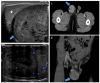

Pre- and post-pubertal testicular tumors are two distinct entities in terms of epidemiology, diagnosis and treatment. Most pre-pubertal tumors are benign; the most frequent are teratomas, and the most common malignant tumors are yolk-sac tumors. Post-pubertal tumors are similar to those found in adults and are more likely to be malignant. Imaging plays a pivotal role in the diagnosis, staging and follow-up. The appearance on ultrasonography (US) is especially helpful to differentiate benign lesions that could be candidates for testis-sparing surgery from malignant ones that require radical orchidectomy. Some specific imaging patterns are described for benign lesions: epidermoid cysts, mature cystic teratomas and Leydig-cell tumors. Benign tumors tend to be well-circumscribed, with decreased Doppler flow on US, but malignancy should be suspected when US shows an inhomogeneous, not-well-described lesion with internal blood flow. Imaging features should always be interpreted in combination with clinical and biological data including serum levels of tumor markers and even intra-operative frozen sections in case of conservative surgery to raise any concerns of malignity. This review provides an overview of imaging features of the most frequent testicular and para-testicular tumor types in children and the value of imaging in disease staging and monitoring children with testicular tumors or risk factors for testicular tumors.